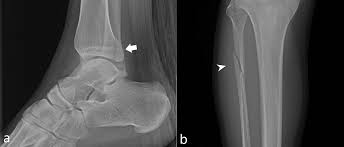

피로 골절이 자주 생기는 부위

피로 골절은 반복적으로 체중이 실리는 부위에서 흔히 발생합니다. 특히 아래 부위는 비교적 자주 언급됩니다.

• 발목과 뒤꿈치 근처